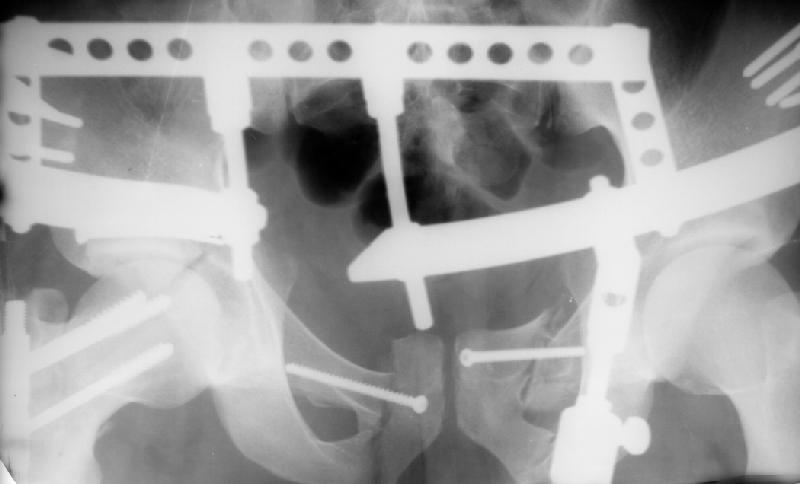

I found inlet and one Judet view. CT is not available - the CT machine is in another building. In the next message i attached three views in external fixator.

See attachment for AP and Judet views after external fixation. Our pelvic guys tried to reduce the acetabulum with the transarticular pin inserted through the lower part of the head. They are satisfied with the pattern and plan to insert a percutaneous screw to fix the position during a surgery for the neck and shaft fracures.

It's still hard for me to see the acetabular fx clearly due to the ex-fix hardware.